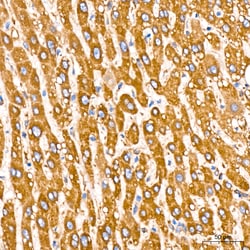

Invitrogen™ GRP94 Recombinant Rabbit Monoclonal Antibody (7P4V7)

| Applications | ELISA, Immunohistochemistry (Paraffin), Western Blot |

Immunogen sequence: EPLLNWMKDK ALKDKIEKAV VSQRLTESPC ALVASQYGWS GNMERIMKAQ AYQTGKDIST NYYASQKKTF EINPRHPLIR DMLRRIKEDE DDKTVLDLAV.

GRP94 is a 803 amino acid protein belonging to the heat shock protein 90 family. It acts as a molecular chaperone that functions in the processing and transport of secreted proteins. GRP94 and its N-terminal fragment stimulates CTL expansion and maturation of human monocyte-derived dendritic cells (MDDC). It plays a central role in innate as well as acquired immunity, maturation and chemotaxis of dendritic cells, Ab production, cross-priming, as a potential marker in breast cancer and is a peptide acceptor in endoplasmic reticulum and an accessory to peptide loading of MHC class I molecules. Expression of GRP94 suppressed A23187-induced apoptosis and stabilized calcium homeostasis. GRP94 is expressed in melanoma or liver metastases of colon carcinoma cells, human gastric carcinoma BGC-823 cells.Specifications

| ELISA, Immunohistochemistry (Paraffin), Western Blot | |

| A synthetic peptide corresponding to a sequence within amino acids 616-715 of human HSP90B1 (NP_003290.1). | |

| Human, Mouse, Rat | |